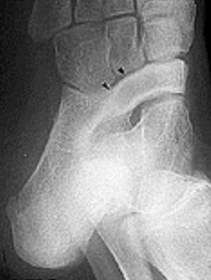

What disease is this? What does the arrow indicate? | Rheumatoid arthritis. Arrow = Bone erosion secondary to inflammation of retrocalcaneal bursa. |